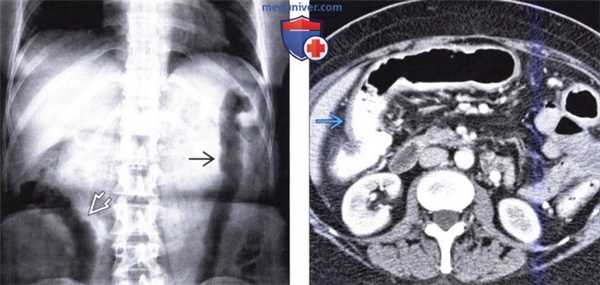

(Слева) На рентгенограмме, выполненной в положении лежа на спине у женщины 55 лет с длительной историей язвенного колита и болью в животе визуализируется относительно ровная ободочная кишка без гаустр с наличием «отпечатков пальцев».

(Справа) На аксиальной КТ у этой же пациентки определяется легкое диффузное утолщение стенки ободочной кишки без существенного накопления контраста слизистой оболочкой а также без явного подслизистого отека — типичных изменений при длительно существующем язвенном колите в сочетании с фиброзом. При колоноскопии было подтверждено, что у пациентки имеет место активный воспалительный процесс лишь в сигмовидной кишке.

(а) На поперечном КТ-срезе определяется утолщение стенки с наличием симптома «жирового гало» (белая стрелка) и сужение просвета прямой кишки.

(б) Пресакральное пространство на сагиттальной реформатированной КТ расширено (черные стрелки) из-за пролиферации жировой ткани.

(в, г) На корональной КТ (реформатированное изображение, КТ-колонография, в) и трехмерной реконструкции с сохранением прозрачности (г) у другого пациента определяется укорочение и сужение сигмовидной кишки, распространяющееся до нисходящей ободочной кишки, с протяженным утолщением стенки и отсутствием гаустральных складок, принятием кишкой трубчатой формы (стрелки). Изменения, определяющиеся на изображениях (а-д), вероятно, обусловлены измененной сократительной способностью ободочной кишки, хроническим воспалением, разрушением слизистой оболочки наравне с патологическими изменениями стенки ободочной кишки (д).

Гипертрофия продольно ориентированной мышечной пластинки слизистой оболочки приводит к укорочению и сужению вовлеченного участка ободочной кишки. Расширение подслизистого слоя и околопрямокишечной области за счет жировой инфильтрации приводит к дальнейшему сужению просвета.

На фоне выраженного изъязвления некоторые участки слизистой оболочки остаются нетронутыми, обусловливая изменения в виде воспалительного псевдополипоза, которые могут быть обнаружены как на КТ при хорошем растяжении ободочной кишки, так и при ирригоскопии с двойным контрастированием. В хронической стадии на КТ обычно определяется утолщение стенки кишки с наличием «гало» (помутнение окружающей жировой клетчатки), сужение просвета кишки и расширение пресакрального пространства из-за гипертрофии мышечной пластинки слизистой оболочки, отложения жира в подслизистой оболочке и околопрямокишечной области. При ирригоскопии с двойным контрастированием просвет пораженной ободочной кишки выглядит суженным, кишка лишена гаустр и укорочена; часто наблюдается также поствоспалительный псевдополипоз (патологическая пролиферация воспаленной слизистой оболочки (Gore et al., 1996; Lichtenstein, 1987).

Потенциально смертельным осложнением является токсический мегаколон, характеризующийся дилятацией ободочной кишки вне наличия обструкции как минимум до 6 см, а также признаками системной интоксикации (Sheth и LaMont, 1998). Изменениями, типичными для этого состояния, являются дилятация ободочной кишки, отсутствие гаустр, часто в сочетании с истончением стенки и нечетким узловым «рисунком» внутреннего края кишки при обзорной рентгенографии и КТ (Thoeni и Cello, 2006). Панколит и хронический язвенный колит ассоциированы с повышенным риском колоректального рака. Так, плоский или инфильтративный рак этой локализации трудно обнаружить на ранних стадиях при ирригоскопии с двойным контрастированием и даже при колоноскопии. КТ-признаками, позволяющими предположить наличие сопутствующей опухоли, являются выраженное асимметричное утолщение стенки и отсутствие дифференцировки ее слоев (Thoeni и Cello, 2006; Gore et al, 1996).